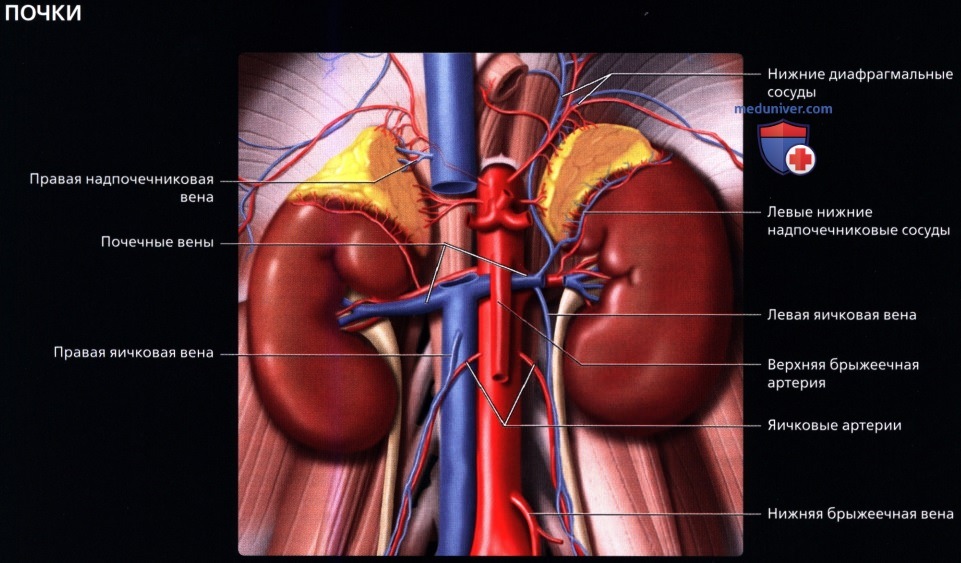

а) Анатомия почек:

2. Топографическая анатомия почки:

• Лежат в забрюшинном пространстве, окружены почечной фасцией (фасция Героты)

• У взрослого каждая почка около 9-14 см в длину и 5 см в ширину

• Обе почки лежат «на» квадратных мышцах поясницы, латеральнее поясничных мышц

3. Внутренняя структура:

• Почки можно рассматривать как полый орган, просвет которого занят жировой тканью, почечной лоханкой, чашечками, сосудами и нервами

• Ворота почки: сюда подходят артерия и вена и выходит мочеточник

• Почечная лоханка: расширение верхнего конца мочеточника в виде воронки:

о Собирает мочу от больших чашечек (2 или 3), каждая из которых в свою очередь собирает мочу от малых чашечек (2-4)

• Почечный сосочек: точечная верхушка почечной пирамиды, содержащей собирательные трубочки, выделяющие мочу

о Каждый сосочек открывается в малую чашечку

• Корковое вещество почки: периферическая часть, содержит почечные (клубочки, сосуды), проксимальные части собирательных трубочек и петли Генле

• Мозговое вещество почки: внутренняя часть, содержит почечные пирамиды, дистальные части собирательных трубочек и петли Генле

• Кровеносные и лимфатические сосуды, нервы:

о Артерия:

— Обычно по одной к каждой почке

— Отходит от аорты на уровне L1-L2 позвонков

о Вена:

— Обычно по одной от каждой почки

— Лежит кпереди от почечной артерии и почечной лоханки

о Нервы:

— Вегетативная иннервация от почечных и аортально-почечных ганглиев и сплетений

о Лимфатическая система:

— К поясничным (парааортальным и паракавальным) лимфатическим узлам